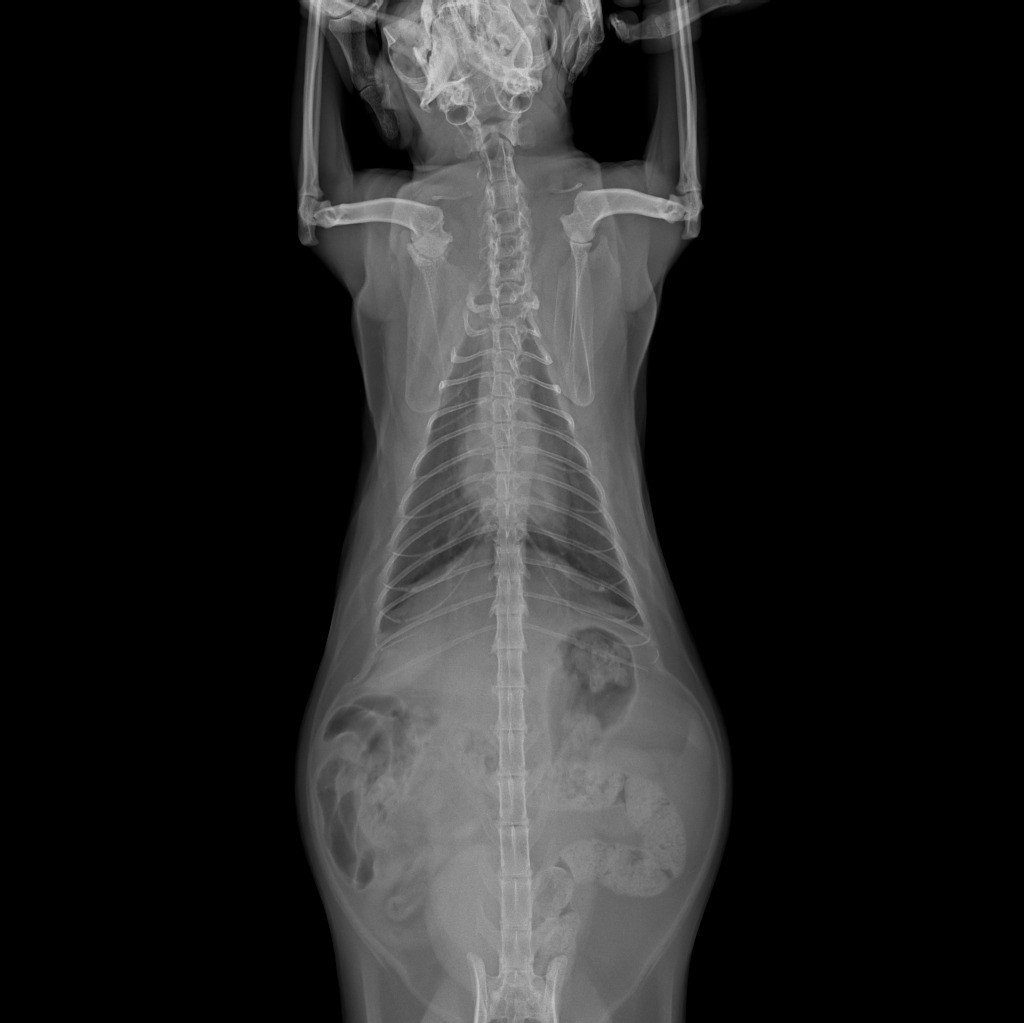

здравствуйте! Кошка начала кашлять, опустив вниз голову и высунув язык трубочкой, шерсть не выходит, длительность приступа около 30сек. Сделали рентген легких по рекомендации ветеринара, сердце проверили, в норме. Посмотрите пожалуйста рентген снимки, что по ним можно сказать?

Здравствуйте. На рентгенограммах видим усиление бронхиального рисунка, что может указывать на хронический бронхит или начало бронхиальной астмы у кошки. Учитывая характер кашля (с вытянутой шеей и языком), вероятна бронхоспазматическая реакция. Рекомендую провести бронхоскопию или хотя бы анализ мокроты (если получится получить), а также рассмотреть ингаляционное лечение (с альбутеролом или флутиказоном).

Здравствуйте. На снимках нет явных признаков новообразований или отека легких, сердце действительно в пределах нормы. Однако в дорсовентральной проекции отмечается небольшое затемнение в каудальных отделах легких это может быть связано с воспалением или астматическим компонентом. Кашель может быть реакцией на аллерген или накопление слизи. Обратитесь к ветеринарному аллергологу или продолжите диагностику по плану. Если приступы станут чаще тогда стоит срочно обсудить назначение пробного курса бронхолитиков.